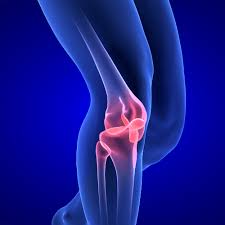

• 무릎까지 이어지는 불편감

이러한 변화는 몸이 통증을 피하려는 보상 작용으로 나타나며, 장기적으로는 허리나 무릎 통증으로 이어질 수 있습니다.

A. 보행 이상과 함께 무릎·허리 통증으로 이어질 수 있습니다.